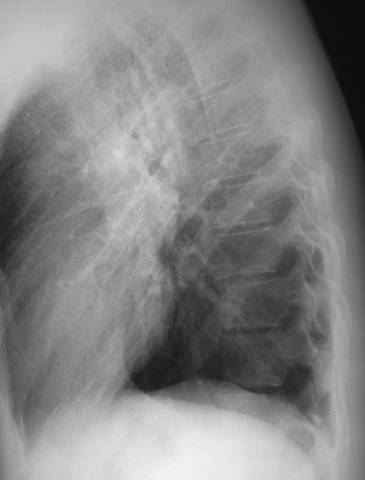

Sarcoidosis with enlarged lymph nodes in chest x-ray (lateral view). Sarcoidosis in chest x-ray. Peripheral hilar lymph nodes are enlarged. For PA view, see Sarcoidosis with Enlarged Lymph Nodes in Chest x-Ray (Pa View).

Picture: Duodecim Medical Publications Ltd